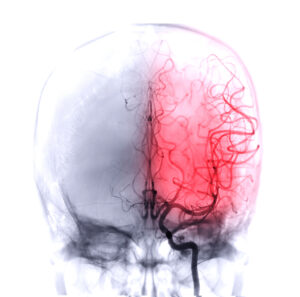

What Are The Common Causes Of A Blood Clot?

Deep Vein Thrombosis (DVT) And Pulmonary Embolism

Blood clots are semi-solid masses which can form in arteries and veins to prevent excessive bleeding. Usually, blood clots disappear by themselves, and clotting is essential for wounds to heal. However, if they start moving across the veins towards the organs and are untreated, they may cause conditions like:

- Stroke